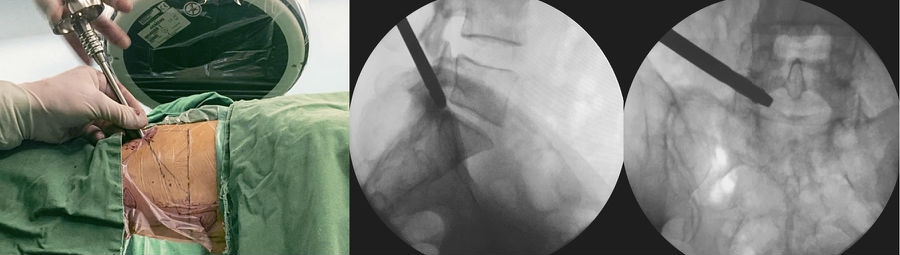

(一)经皮内镜下椎间孔入路腰椎间盘突出切除术

经皮内镜下椎间孔入路腰椎间盘突出摘除术(transforaminal percutaneous endoscopic lumber disectomy,TF-PELD)是在局麻下经腰椎侧后方入路进入椎间盘内或神经根与硬膜囊前间隙,直接摘除脱出或游离的椎间盘组织,一般不需特别牵拉神经根和硬膜囊,对椎管内结构干扰较小,不易导致传统后路经椎板间隙入路所致的椎管内粘连。手术步骤如下:

1. 体位

患者取侧卧位,患侧在上,健侧腰部垫高,以健侧髂骨刚离开床面为宜。(图3)

2. 手术入路

取后外侧入路,穿刺点L3~4为后正中线旁开 8~10cm,L4~5为 10~12cm,L5~S1为12~14cm,肥胖者各节段较普通患者多旁开1~2cm。(图 4)

3. 麻醉

使用1%利多卡因40ml进行逐层局部浸润麻醉,包括皮下组织、深筋膜和关节突关节。(图 5)

4. 穿刺

以L5~S1为例,根据髂嵴的高低,针尾向头侧倾斜约 40°~60°,外展角约 30°~50°,定位针在正位X线透视下刚好位于后背正中的棘突连线上,侧位X线透视下则紧贴上关节突腹侧,下缘位于下位椎体的后上缘。(图6)

5. 穿刺点

做大约1cm皮肤切口,用导丝置换穿刺针,沿导丝用扩张器逐级扩大软组织。(图7、图8)

6. 置入定位器

在上关节突上打孔,退出扩张器,再磨除部分关节突关节,逐级扩大椎间孔。(图9~图13)

图3 定位板前后位X线片标定靶点和穿刺方向

A. 术前定位板标记体表位置;B.定位板X线射片投影图

图4 标记穿刺线

A. L5-S1椎间盘平面;B.棘突中线连线;C.穿刺假想体表投影

图5-图9 A:使用利多卡因进行局部分层麻醉(皮肤、皮下组织、筋膜、关节突周围);B:穿刺针X线片侧位投影图;C:穿刺到位后交换导丝;D:导丝引导下通过导杆、三级套管扩张肌肉及软组织;E:导丝引导下交换Tom针,定位上关节突

图10 Tom针定位上关节突

A. Tom 针定位上关节突;B.Tom 针X 线片侧位投影图;C.Tom 针X线片前后位投影图

图11-图13 6mm扩孔骨钻扩孔过程中;6mm扩孔骨钻侧位X线片投影图;8mm扩孔骨钻前后位X线片投影图

7. 置入工作套管

将7.5mm外径的工作套管置入椎间孔,并沿工作套管放入椎间孔镜。(图14、图15)

图14-图15 工作套管到位,X线片投影图显示套管头端位于椎管腔内;内镜下手术操作

A. 侧位;B.前后位